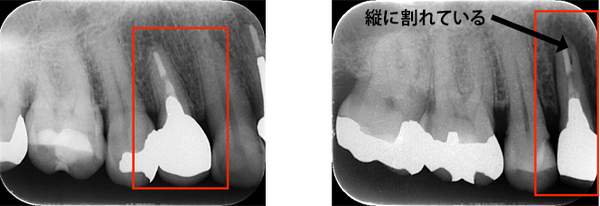

こちらの写真は違和感があるということでレントゲンを撮ったが異常は見つからなかった。しかし、1ヶ月後にもう一度撮影すると、歯が割れているのがわかりました。また、歯の周りの骨の部分がやや黒くなっているのも分かります。

また、金属の土台がはいっていなくても、根の治療を行った歯にブリッジが入っている場合、負担が大きくなり、

神経がある歯よりも脆い神経を取った歯は割れてしまうことがあります。

ブリッジが取れたということでご来院患者様でした。レントゲンを撮ると縦に割れていました。

歯を抜くと、やはり割れていました。